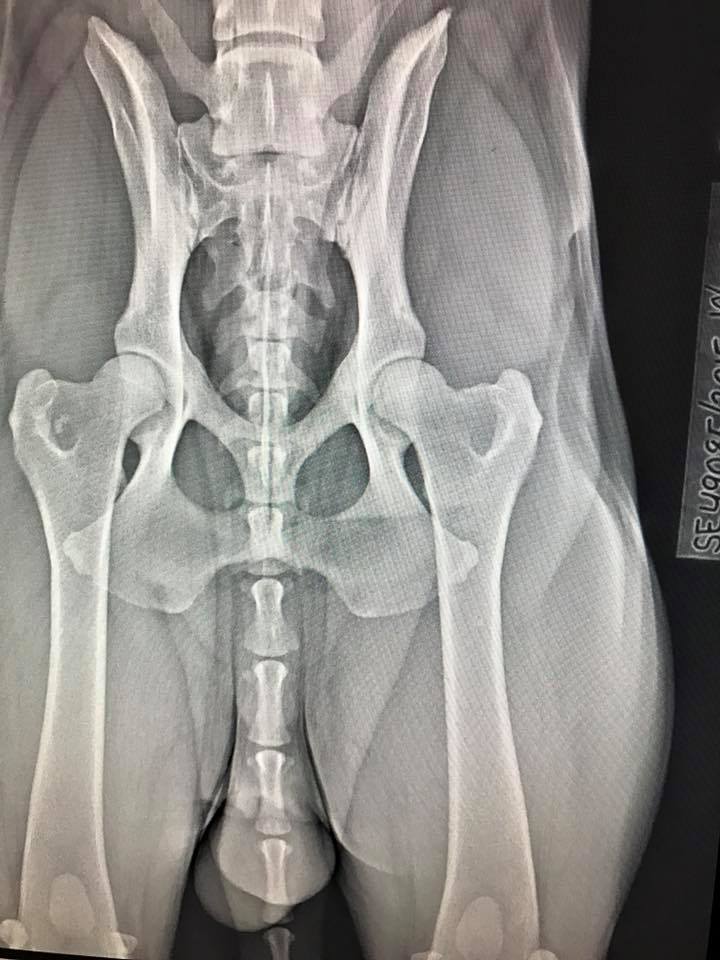

yoshihd ← Föregående Nästa → HD A/A Dela detta: Dela på Facebook (Öppnas i ett nytt fönster) Facebook Dela på Pinterest (Öppnas i ett nytt fönster) Pinterest Dela på Instagram (Öppnas i ett nytt fönster) Instagram Gilla Laddar in …